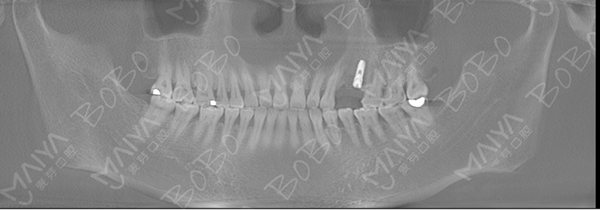

在麦芽口腔举办的"全程寻找缺牙人,免费种牙"公益活动中,赵女士成为首批免费种牙的幸运儿,麦芽口腔硕博种植专家团在对赵女士的牙齿情况做了综合检查深入分析指出,赵女士当前情况为左上4/5牙长期缺失,牙槽骨已经出现一定程度的萎缩吸收,如果长期以往不仅牙槽骨吸收越来越严重,也会影响到邻牙的健康,增加后期修复的难度。从X光全景片上,还可以看到,由于长期单侧咀嚼食物,患者脸型已经出现轻微偏脸畸形,影响了面部美观。

赵女士种牙前口腔全景ct

由于赵女士长期牙缺失,牙槽骨已经出现萎缩吸收,导致两边邻牙倾斜,因此她的牙缺失间隙在动态变小,牙齿的间隙不够种植两颗牙的位置,但是种一颗牙又显得空间有点偏大,最终专家团经综合考虑,采用麦芽MAC数字化种植技术,数字化精确导航种植,采取了种植一颗连冠修复的方式,只需一颗种植钉就可以达到修复两颗牙齿的目的,仅仅不到一个小时就帮赵女士种上了牙齿。

种牙成功后口腔ct全景片